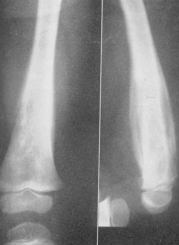

RAHITISMUL PRECOCE apare la sugarul de 6-8 luni.

Radiologic:

Zona provizorie de calcificare se lateste, ia forma de cupa cu concavitatea spre epifiza, devine neregulata, zimtata, osteoporotica, uneori stearsa pâna la disparitie;

Cartilajul de conjugare este latit, neregulat delimitat astfel încât nucleul de osificare epifizar este îndepartat de diafiza. Nucleii de osificare epifizari apar târziu si sunt decalcificati.

La nivelul diafizei are loc o decalcificare care duce la subtierea corticalei, încurbari ale oaselor, fracturi pe os patologic, largirea canalului medular. În cazul în care oasele se încurbeaza, pe partea concava a osului apar apozitii periostale. În perioada de vindecare apare o noua linie provizorie de calcificare, oasele se recalcifica, apar nucleii de osificare epifizari corespunzatori vârstei, deformarile osoase si fracturile se calcifica.